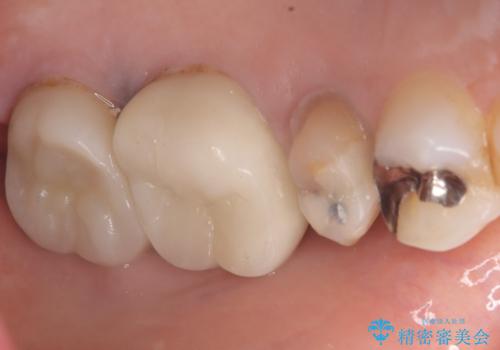

- 主訴:いつも物が詰まる場所があり気になる。衛生士に被せものと土台の境目に汚れが溜まっている箇所があると指摘され気になっている。

過去に入れた被せものと土台の歯との適合が悪く、隙間が出来ておりそこに汚れが溜まりやすい状態になっていました。セラミッククラウンでのやり替えとなりました。

唇側マージン不適なこと説明し、審美性・適合性に優れたセラミッククラウン(スタンダード)でのやり替えとなりました。